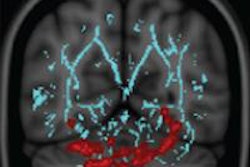

The research, led by Michael Cima, MIT professor of engineering, uses contrast agents, magnetic fields, and radio waves to interact with protons to produce detailed images of the body's interior.

The imaging technique combines two forms of silicone -- a solid called (PDMS) and a substance known as DDMPS, which has an oily consistency. The oily DDMPS can be dissolved in PDMS, creating what's called a "swollen polymer."

The polymer is shaped into a 1.5-mm sensor that can be implanted in tissue during a biopsy along with smaller particles that can be injected through a needle. After injection, these particles clump together to form a solid sensor.